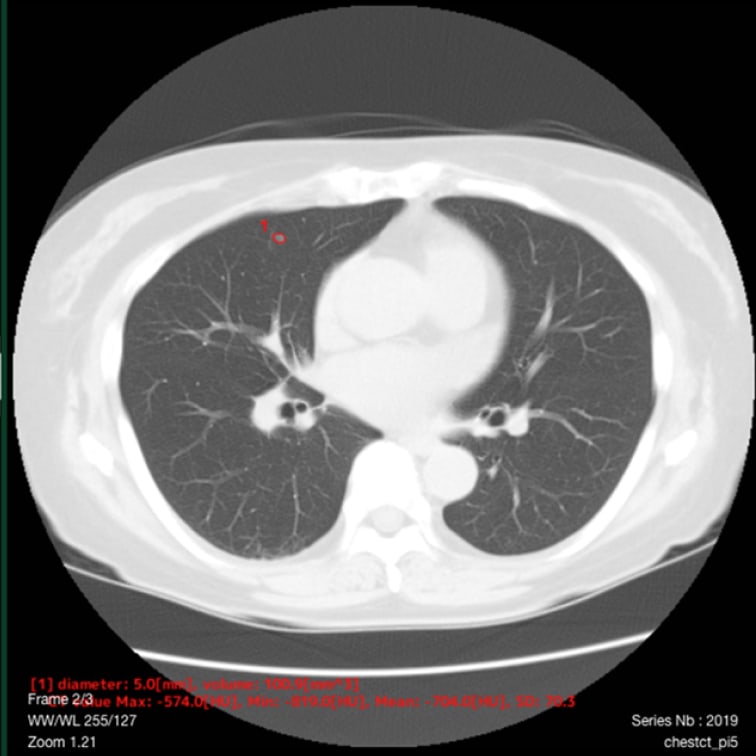

以下の肺結節候補領域を検出して表示します- 充実型:3mm以上30mm以下

- 部分充実型:5mm以上30mm以下

- すりガラス型:5mm以上30mm以下

- 自動計測

- 検出した候補領域の大きさ:体積 [mm³] およびAxial断面最大径 [mm] を出力

- CT値:最大・最小・平均値・標準偏差を出力

解析事例

標準線量CT